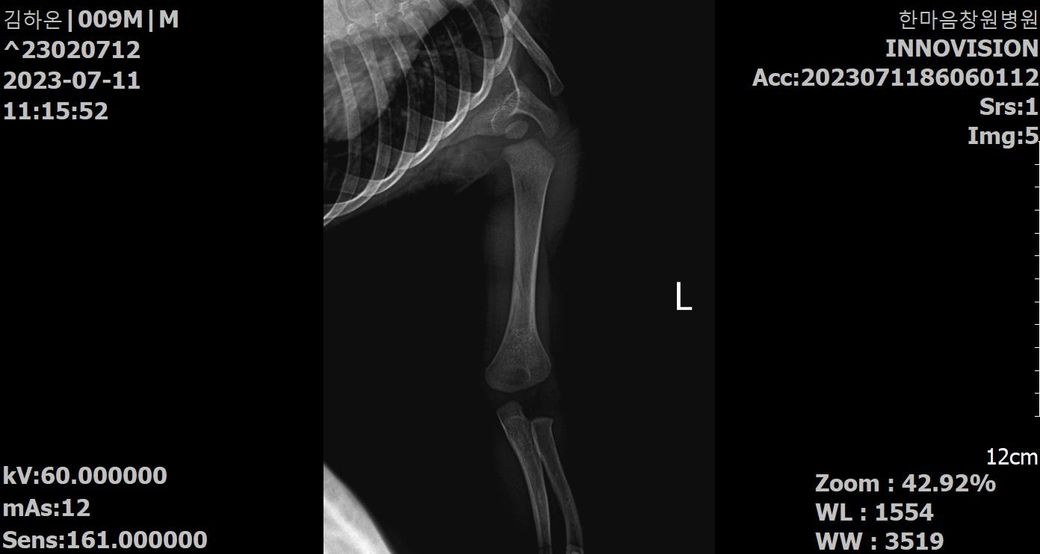

첨부된 파일에 기재된 사실과 같이 23년 5월 24일 촬영된 양팔 X선 2장과

23년 7월 11일 촬영된 양팔 X선 2장입니다.

양팔이 골절이 되었었는데요,

3) 5월 24일 X선에 비해 7월 11일 X선은 또한 어떤 치료단계인지 문의드리고자 합니다.

4) 종합하자면 3월 초~ 중순에 골절이 일어났다고 보는게 타당한지?

• 2번 째 사진